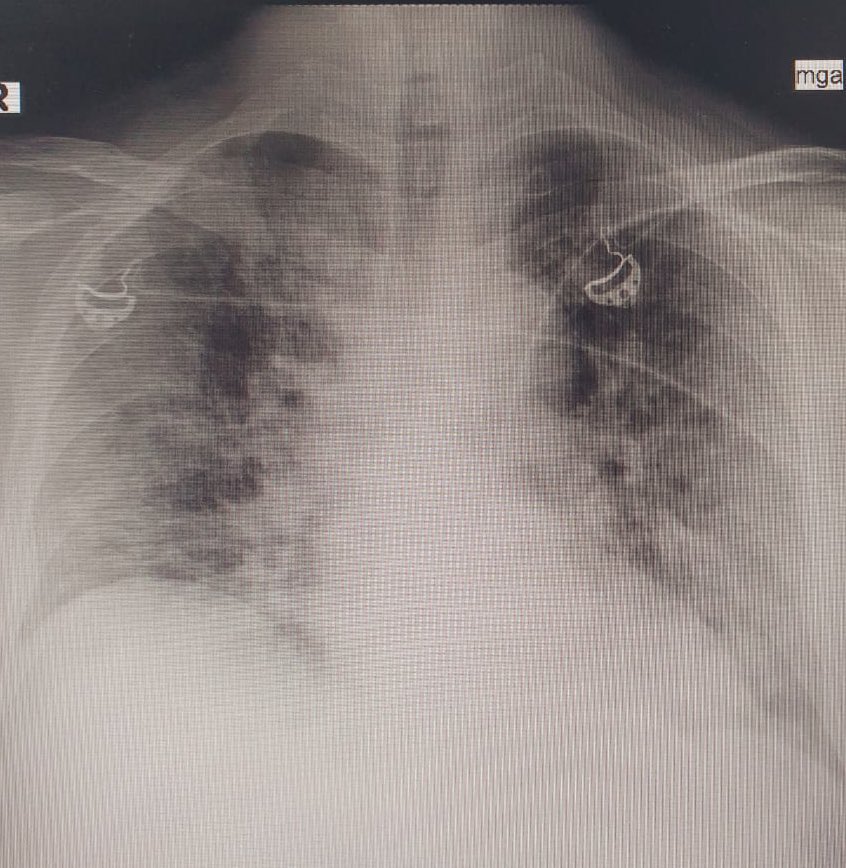

ثالثاً والأهم "أشعة الصدر" chest x-ray

لنحدد هل نزل الالتهاب على الصدر و ما هي حدته.

تنقسم الرئة لجزء أيمن يُقسم بدوره إلى فصين وأيسر يُقسم إلى ثلاثة فصوص ، كوفيد غالباً يبدأ التهابه من "الأطراف/الأضلاع" في الفصوص السفلية من الرئة وغالباً في الجهتين

هذه صور لأشعة صدر طبيعية ( سوداء والقلب في المنتصف ) وأشعة صدر غير طبيعية ، البياض الذي ترونه في الصور الأخرى هو الالتهاب ودرجاته تختلف بالطبع ، كم فص من الرئة أصيب ؟ وماهي الوظائف الحيوية للمريض وقتها و فحوصاته الأخرى